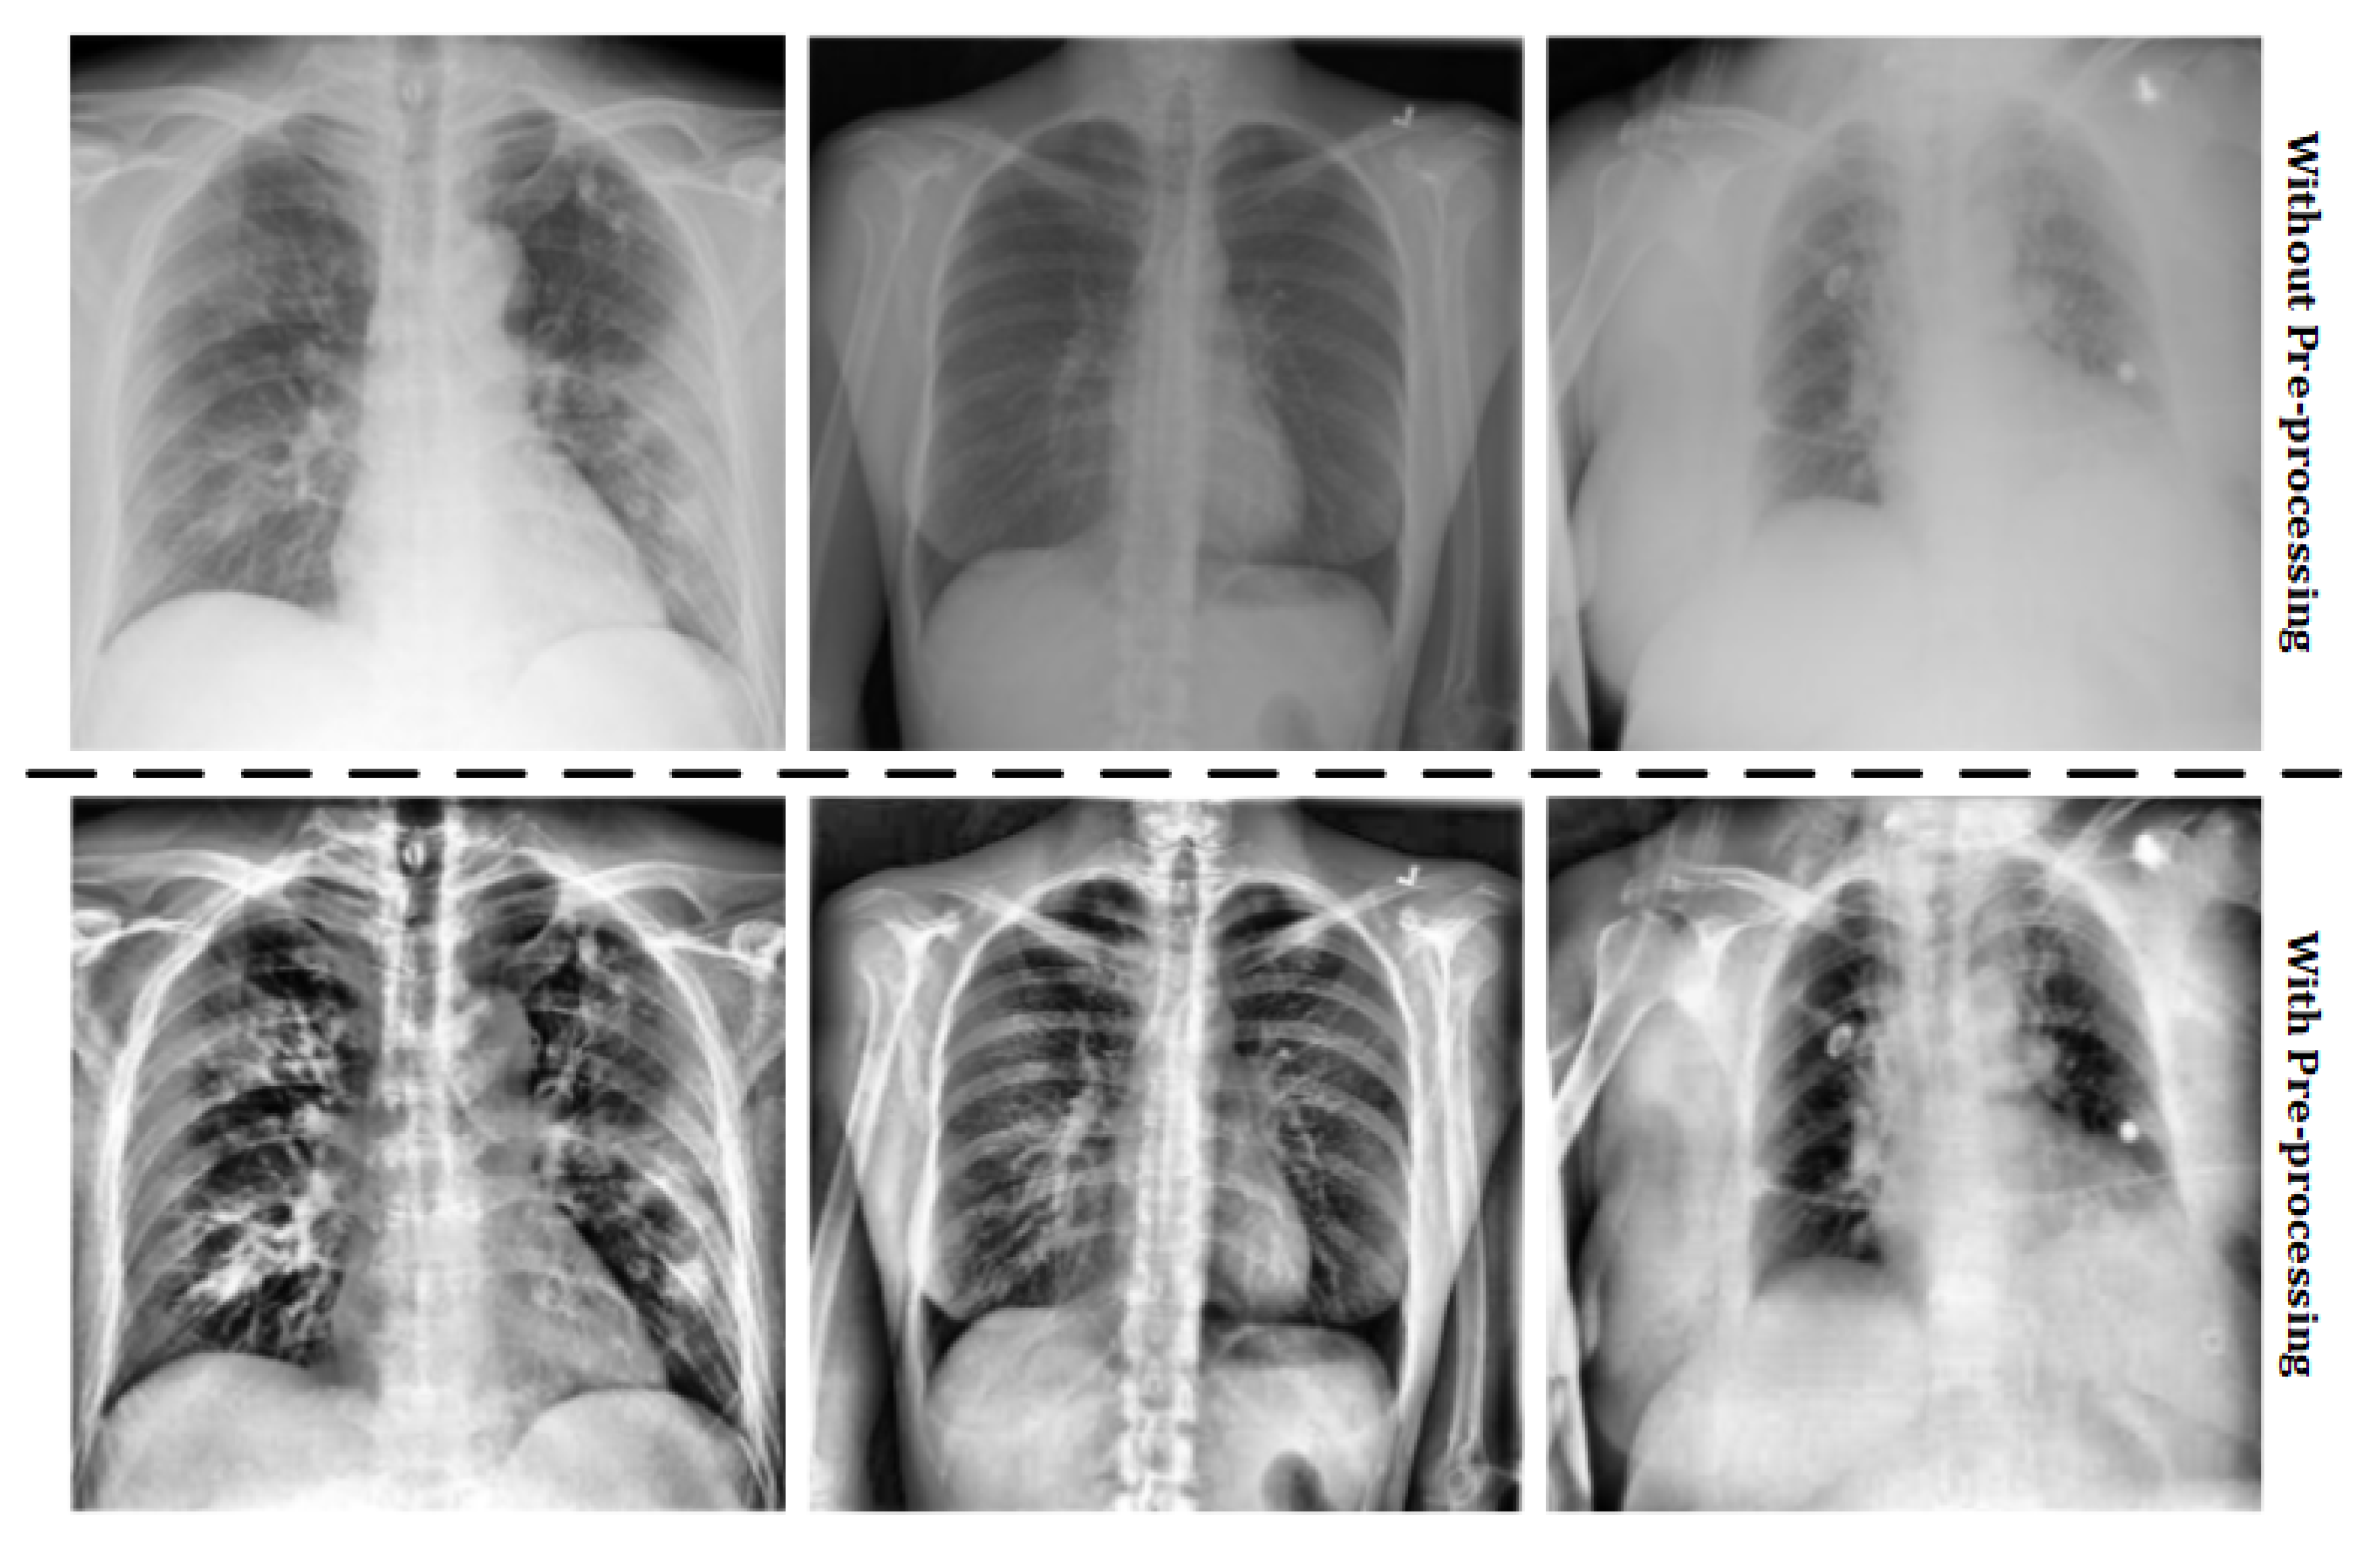

- Pre-processing: the images stored in the original dataset contains lung X-ray images of healthy patients, patients with pneumonia and COVID-19 positives. However, some images of the COVID-19 positive cases were not obtained with the same parameters as detailed above, so these images must not be taken into account. Moreover, in order to work with images of the same characteristics, an histogram equalization is applied. These two treatments compose the pre-processing stage. The results of the pre-processing step can be observed in Figure 2.

Figure 2. Pre-processing results. - Training: using TensorFlow framework with Keras, a VGG-16 architecture [22] is implemented and combined with a final inference layer to train a classification system with three classes (healthy, pneumonia and COVID-19). The output of this stage is the convolutional neural network model.

A pre-processing stage was done to all the X-ray images due to be obtained from different machines with different calibrations, which caused a significant variation in the histogram of the images.